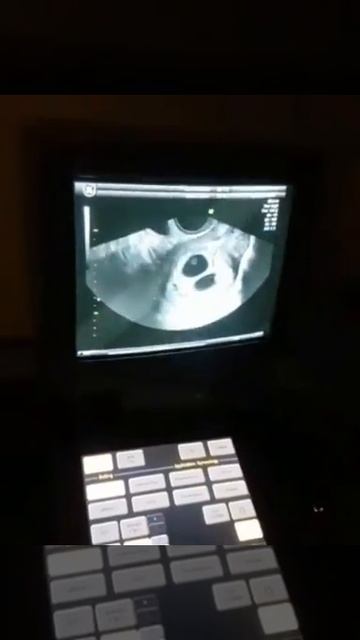

ТРОЙНЯААА!В ЕСТЕСТВЕННОМ цикле!

У моей пациентки с диагнозом Бесплодие. Бывает и так Всем привет и волшебного зимнего вечера, видео от 2025-04-26 загрузил на rutube Пещера тайн и секретов...